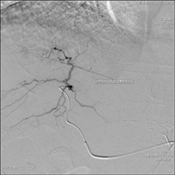

An arteriogram on the tumor in the left segment was performed to determine the blood supply to the remainder of the tumor. Guided by Innova’s excellent image quality, the catheter was repositioned and Ringold re-embolized the vessel supplying blood to the remaining 15 percent of the mass. A repeat arteriogram helped Ringold to confirm the success of the embolization.

His focus then shifted to the nodule in the right lobe. Using Innova CT, a 3-D CT of the liver was performed. It clearly showed the artery that was supplying the nodule. Ringold repositioned the catheter to embolize the vessel.